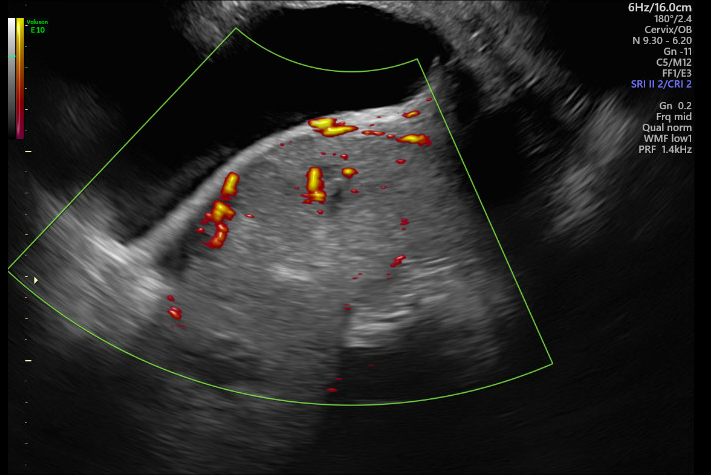

Potential Placenta Accreta

A placenta previa paired with suspected accreta was identified and tracked throughout this pregnancy. With a previous history of two cesarean sections along with a suspected accreta and previa, a third cesarean was scheduled for 34 weeks. The delivery plan would also involve an immediate hysterectomy given these indications.

When the patient delivered, everyone was surprised to discover no accreta, although placenta previa was still present. The patient and baby were both healthy, and the hysterectomy was not performed.